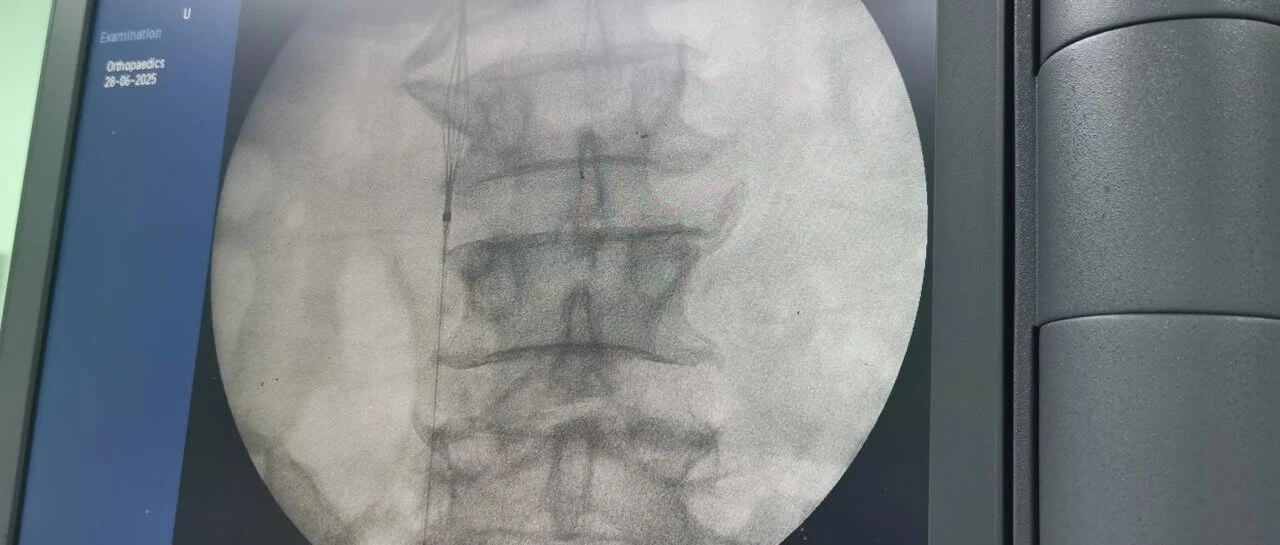

面對這一嚴(yán)峻挑戰(zhàn),羅軍副院長團(tuán)隊果斷決策,先行實(shí)施“下腔靜脈濾器植入術(shù)”。手術(shù)團(tuán)隊?wèi){借精湛的技術(shù),在患者的下腔靜脈(人體最大的靜脈干)內(nèi)精準(zhǔn)放置了一個特殊的“濾網(wǎng)”裝置——腔靜脈濾器。它的核心作用就是充當(dāng)“血栓攔截網(wǎng)”:

攔截脫落的血栓:有效捕捉從下肢深靜脈脫落的血栓碎片,防止其隨血流進(jìn)入心臟和肺部。

預(yù)防致命肺栓塞:從根本上大幅降低患者在骨折手術(shù)期間及術(shù)后康復(fù)階段發(fā)生肺栓塞的風(fēng)險。

保障后續(xù)手術(shù)安全:為接下來必須進(jìn)行的、耗時較長的骨盆髖臼粉碎性骨折修復(fù)手術(shù)(尤其是利用3D打印技術(shù)進(jìn)行的精準(zhǔn)手術(shù))掃除了最大的安全隱患,提供了至關(guān)重要的手術(shù)安全保障期。